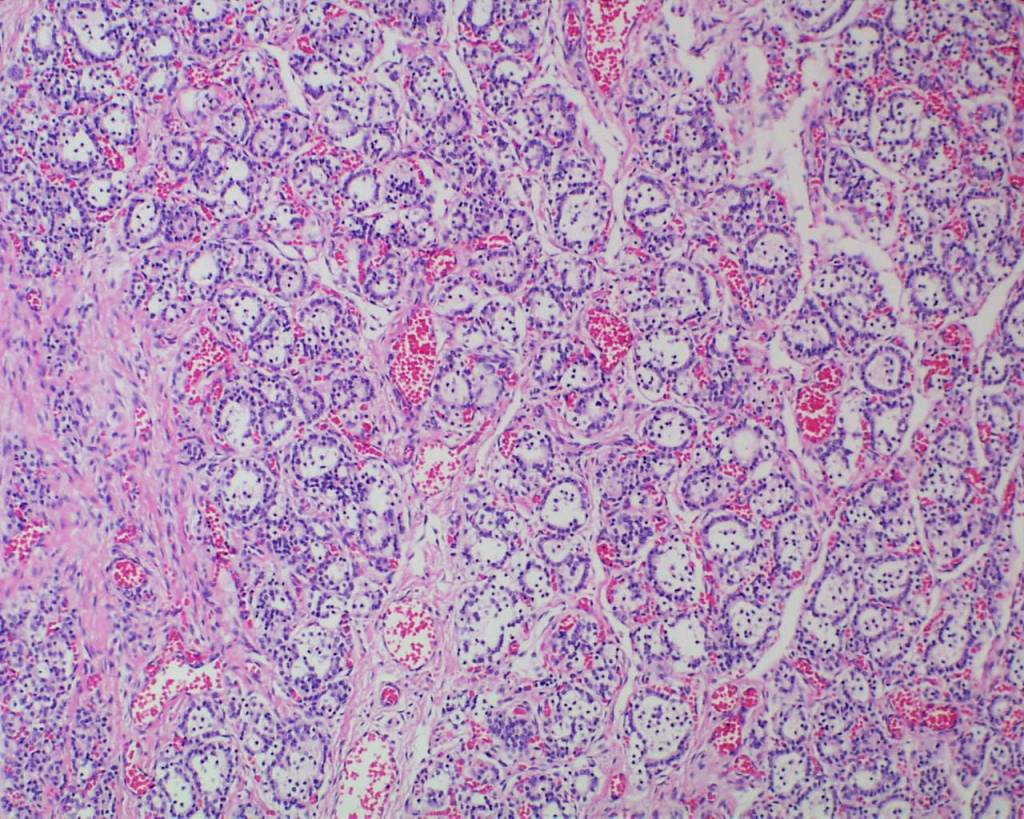

Colloid in follicles: Temperature modulation in utero is to a large extent controlled by the mother’s body’s temperature. The developing thyroid does accumulate iodinated protein within variable size follicles. Circulating thyroid hormone in the fetus is mostly reverse T4 which prevents overheating of the fetus in the body-temperature water bath of amniotic fluid. TSH is produced in the fetal hypothalamus and placenta at a basal rate. However, with birth, there is TSH surge that results in release of active thyroid T3 and T4 that initiates necessary thermogenesis in the fetus3. This surge occurs within the first 15 minutes. In the sheep, if a lamb is delivered but the attachment of the umbilical cord remains functional to the placenta, the externalized lamb will become hypothermic. Cutting the cord initiates the surge of TSH and epinephrine necessary to maintain body temperature outside the womb.

This histology of loss of follicular colloid in the 24 to 48 hours after birth has been documented in newborn infants at autopsy4 (Fig 3a-c).

In stillborn infants the extent of colloid in the thyroid follicles and mononuclear cells in the follicles varies. Some variability may be due to gestational age differences (Fig 4a, b).

Another variable may be the effect of autolysis, but this has not been carefully correlated with postmortem retention intervals. Correlations of thyroid histology with disease in the newborn infant has been studied5. There is not a study correlating the changes in colloid with other findings in stillbirth, such as evidence of acute asphyxia or thymic involution.